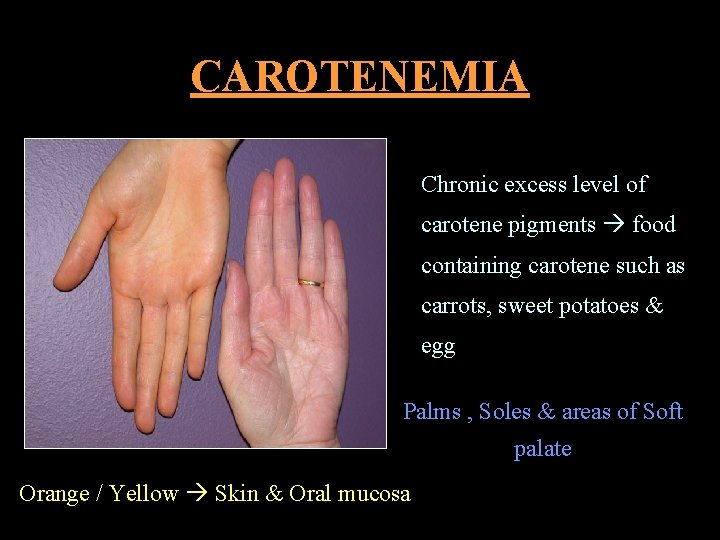

CAROTENEMIA Chronic excess level of carotene pigments food containing carotene such as carrots, sweet potatoes & egg Palms , Soles & areas of Soft palate Orange / Yellow Skin & Oral mucosa